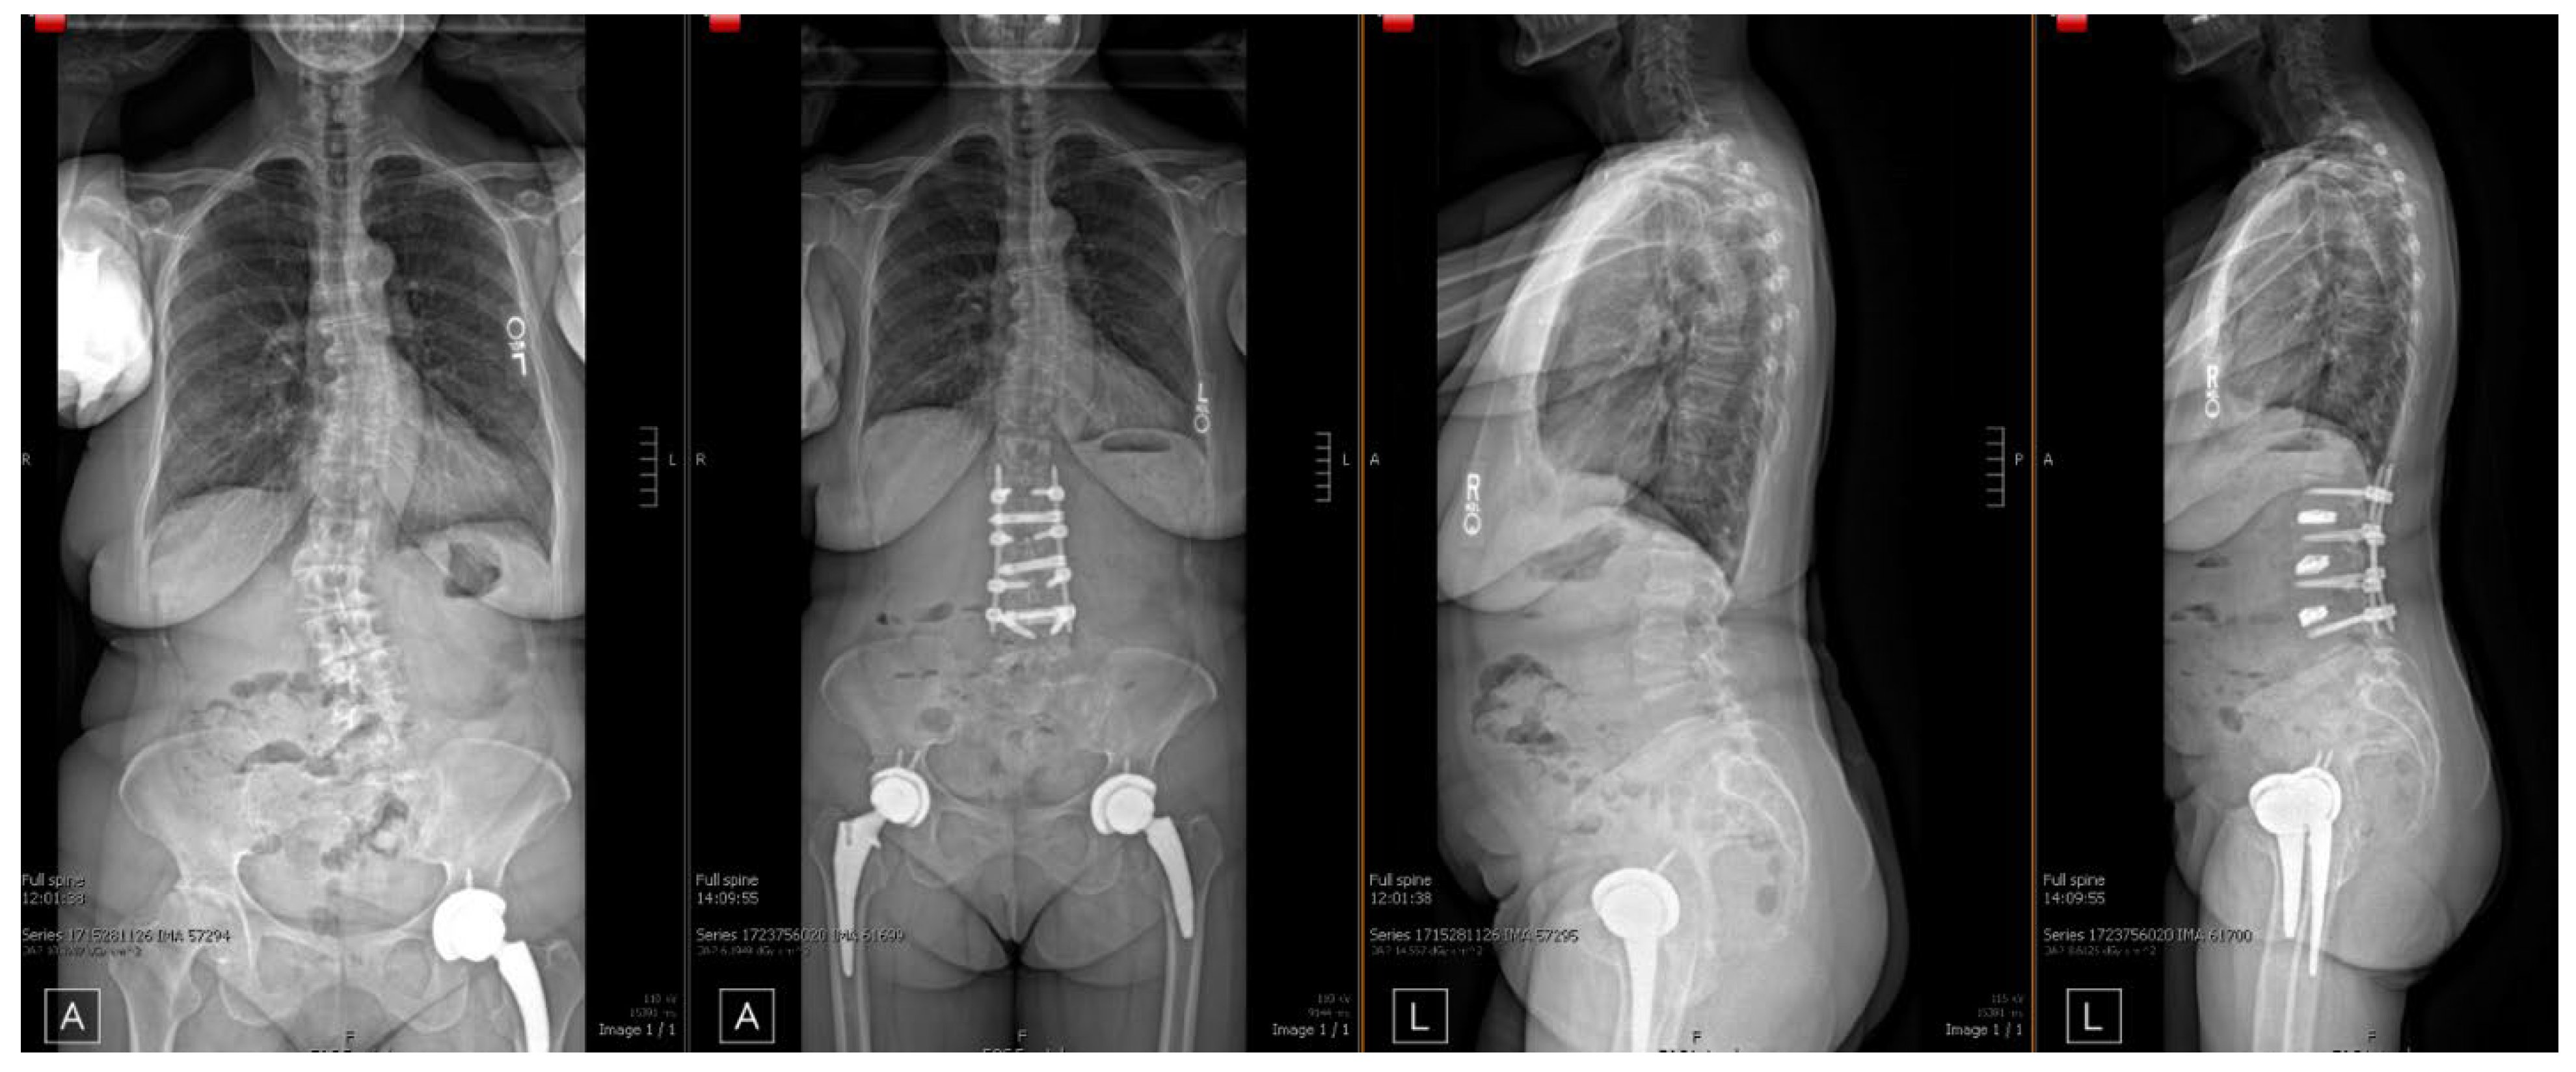

| Patient No. | Age | Sex | BMI | Pre-Operative Diagnosis | Procedure(s) |

|---|---|---|---|---|---|

| 1 | 75 | M | 21.9 | - Adjacent segment disease L2–L4 - Lumbar Radiculopathy | (1). Hardware Removal (2). L2-5 Revision MIS PSF (3). L2-L4 PTP XLIF |

| 2 | 66 | F | 27.4 | - Degenerative Scoliosis - L2–L5 Lumbar Stenosis | (1). L2-5 XLIF |

| 3 | 69 | F | 20.7 | - L3–L4 spondylolisthesis | (1). L3-4 XLIF (2). L2-L5 MIS PSF |

| 4 | 65 | F | 27 | - L3–L4 spondylolisthesis | (1). L3-4 PTP XLIF (2). L3-4 MIS PSF |

| 5 | 71 | F | 34.7 | - Spinal Stenosis w. neurogenic claudication | (1). L3-4 XLIF (2). L3-4 PSF |

| 6 | 64 | M | 37.2 | - Scoliosis of lumbar spine | (1). L2-5 XLIF (2). L2-5 PSF |

| 7 | 78 | M | 34.1 | - Spinal stenosis without neurogenic claudication | (1). L2-5 PSF (2). L2-5 XLIF |